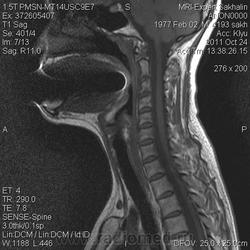

МРТ ШОП

Женщина с жалобами на боли в пояснице, но решила обследовать весь позвоночник.Травм, операций не было.Такие же изменения в грудном отделе.

1. Субархноидальная киста

2. Лизированная субдуральная гематома.

3. Менее вероятнее эпиема (но это только при условии соотвествующей клиники...)

Думаю все же №1... № 2 - это запасной вариант. Послушаем, что скажет общественность

Мультилокулярная экстрадуральная менингеальная киста